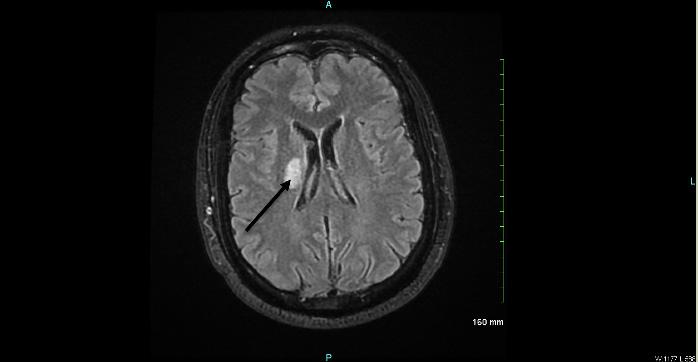

During her stay overnight, the rapid response team was activated for an acute mental status change, with last known well three hours prior. The patient was minimally responsive to pain with snoring respirations and a National Institute of Health Stroke Scale score of 22. On physical exam, the right pupil was 1 mm in diameter and reactive to light, and the left pupil was 4 mm and nonreactive. An emergent stroke workup was initiated, and CT angiography (CTA) of her head showed multifocal occlusions of the left posterior cerebral artery (PCA) (Image 1). The stroke neurologist communicated concerns for proximal basilar artery occlusion, and the patient was taken for emergent mechanical thrombectomy. Basilar tip occlusion was found. Thrombolysis in cerebral infarction grade 3 reperfusion was achieved after first pass, and the patient was admitted to the neurointensive care unit. The patient expired during her stay, which was complicated by development of aspiration pneumonia.

The patient was admitted to the medical intensive care unit for further management. Repeat CT head without contrast was done a day after admission due to a decrease in responsiveness, showing acute infarcts in the bilateral cerebellar hemispheres and cerebellar vermis with mass effect on the fourth ventricle and rostral hydrocephalus. The initial CTA head result was addended at this time to show diminished flow in the distal basilar artery extending into the origins of the bilateral PCAs compatible with intraluminal thrombus (Image 2). Neurology and neurosurgery were consulted, and the patient was deemed not a candidate for advanced therapies or surgeries, given devastating neurological injury and poor prognosis. The decision was made with family to withdraw care, and the patient expired on the third day of admission.

Image 2. Computed tomography angiography coronal view (Patient 2) with arrow pointing to the site of basilar artery occlusion with bilateral posterior cerebral artery involvement.